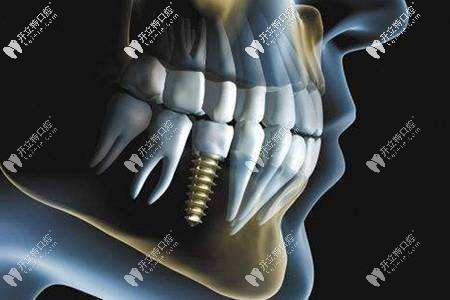

種植牙自不必說了,不僅普通種植牙,還有即拔即種可以實(shí)現(xiàn)拔牙和種植當(dāng)天進(jìn)行,可以說是一項(xiàng)種植牙的福利了。